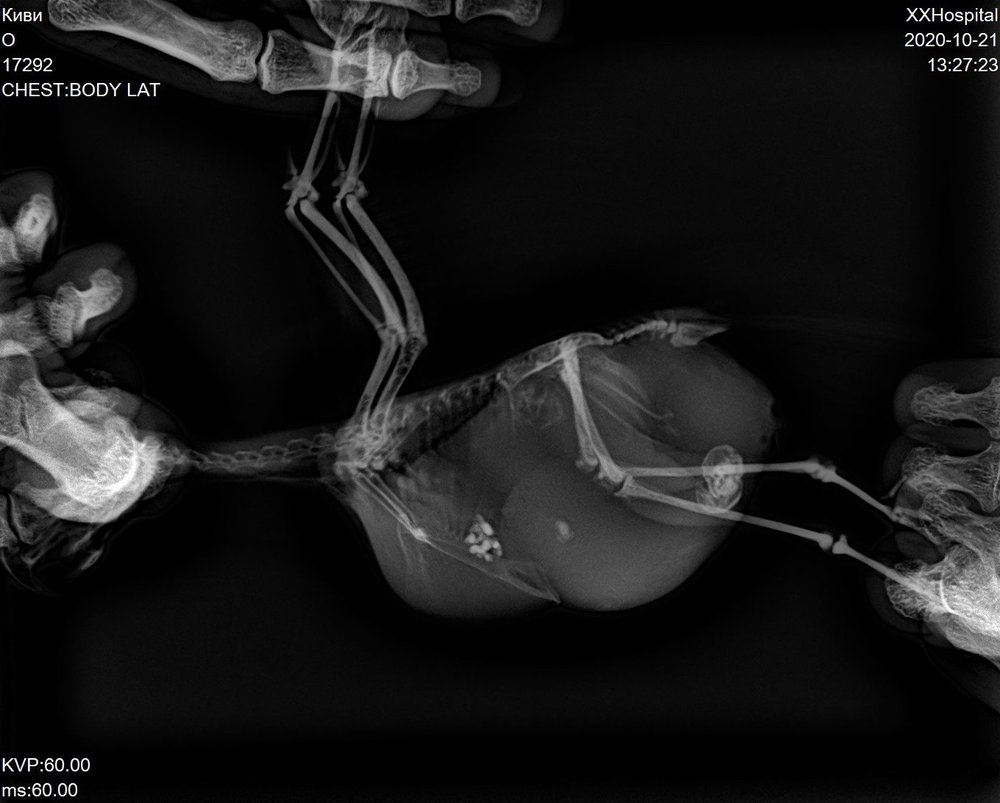

Застряли лопнувшие яйца. Самка какарик.

10. Какие симптомы Вас насторожили? Как они развивались? сидела нахохлившись и тяжело дышала. Отвезли к орнитологу. Сделали рентген и УЗИ. Оказалось внутри застряло 2 лопнувших яйца. Жидкость в брюшной полости. Жидкость откачали 7 мл - зеленая. Назначили Синулокс 1/4 таблетки с 0,5мл воды 2 раза в день. Через 5 дней назначили другой прием, снова сделали рентген. Жидкость снова собралась, откачали 5 мл. Добавили Карсил 35мг по 1/4 растолочь, развести в 1 мл воды давать по 2 м этого раствора. Назначили следующий прием через 7 дней - осмортели, сазалт если жидкость снова будет скапливаться привозить и откачивать. Прошло 5 дней я вижу что брюшко снова раздуто

Это последний ренген

17292_2.jpg